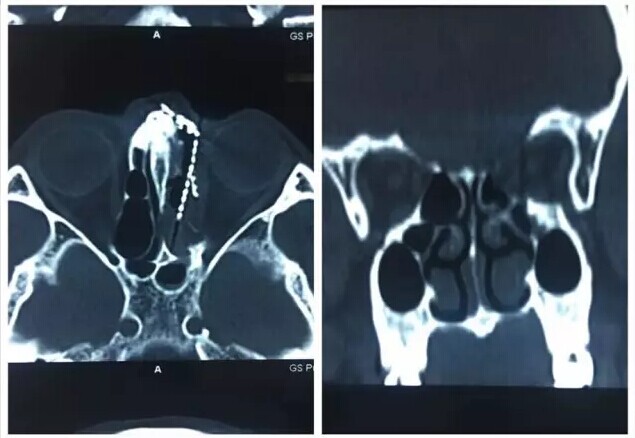

甘肃省二院眼科开展经眼眶视神经减压术使许多外伤失明的患者重见光明------2017-04-28 发布时间:2017-04-28 来源: 作者: